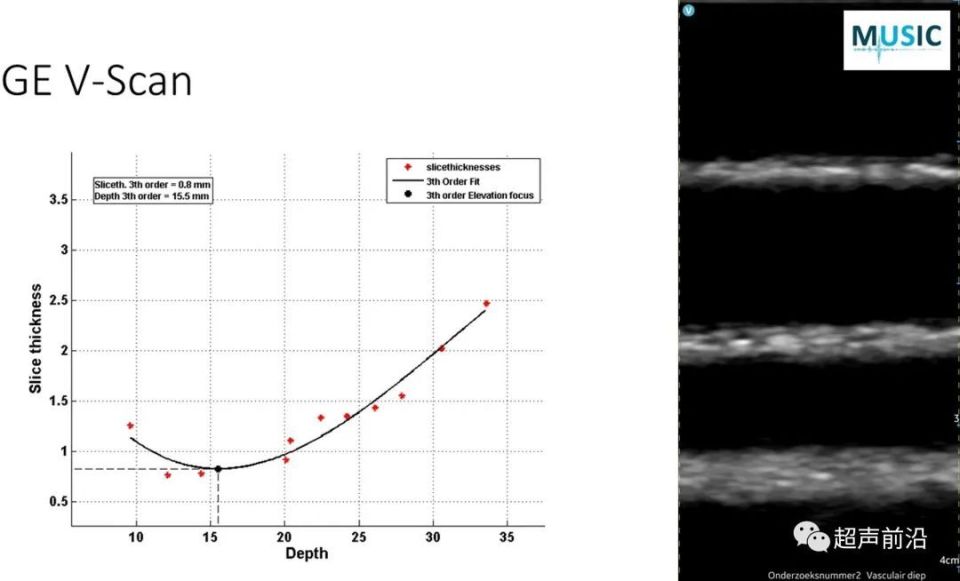

图4:线性阵列切片厚度测量

线性阵列的聚焦深度范围为 1.5 cm (VScan) 至 3.5 cm (Butterfly)。在聚焦深度下,声束宽度从 0.8 到 1.4 mm 不等。在 1 和 2 cm 处,声束宽度在 GE VScan 的 1 mm 到 Butterfly IQ+ 的 4 mm 之间变化。传统超声机器 Affiniti 在所有浅表深度都具有相对恒定的波束宽度。